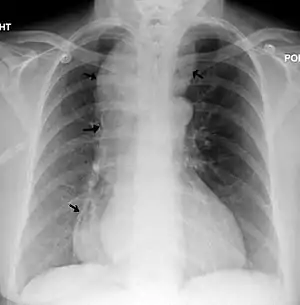

| یک گرافی قفسهٔ صدری که آشالازی را نشان میدهد (نوک پیکان، اتساع بیش از اندازهٔ مری را نشان میدهد) | |